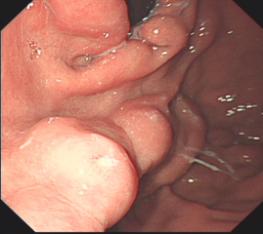

胃底潰瘍并出血止血術(shù)